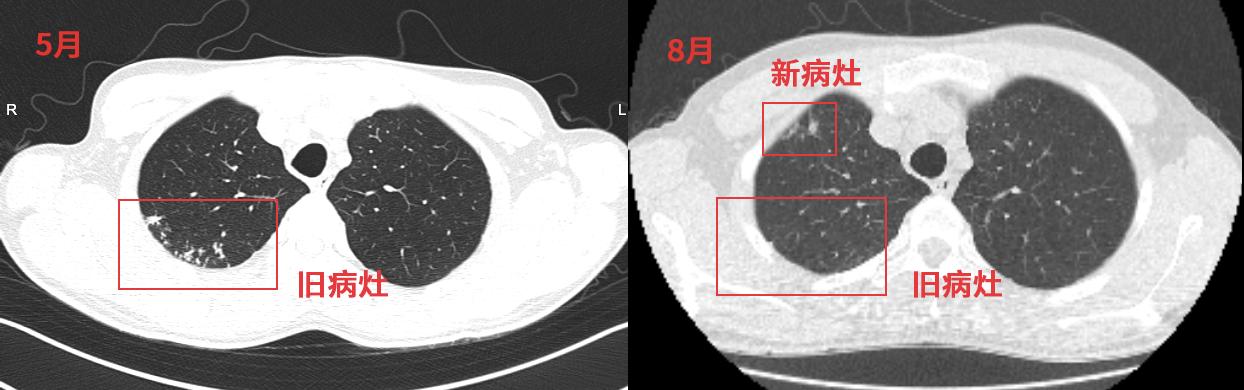

他5月确诊肺结核,到了8月第3次复查时,却发现旧病灶已经明显吸收(备注只是这里的基本吸收完了,其他地方的还在),但是却出现了一些新的病灶,而且新病灶部位也出现了明显的胸痛,还有咳嗽。

这确实不是一个新现象,在治疗过程中,我们经常发现某些结核病人用药之后反而出现了反常性的症状、体征恶化。

我们把这种现象称为矛盾反应(paradoxical reaction,PR), 指原有病变恶化,或者出现新的病变。